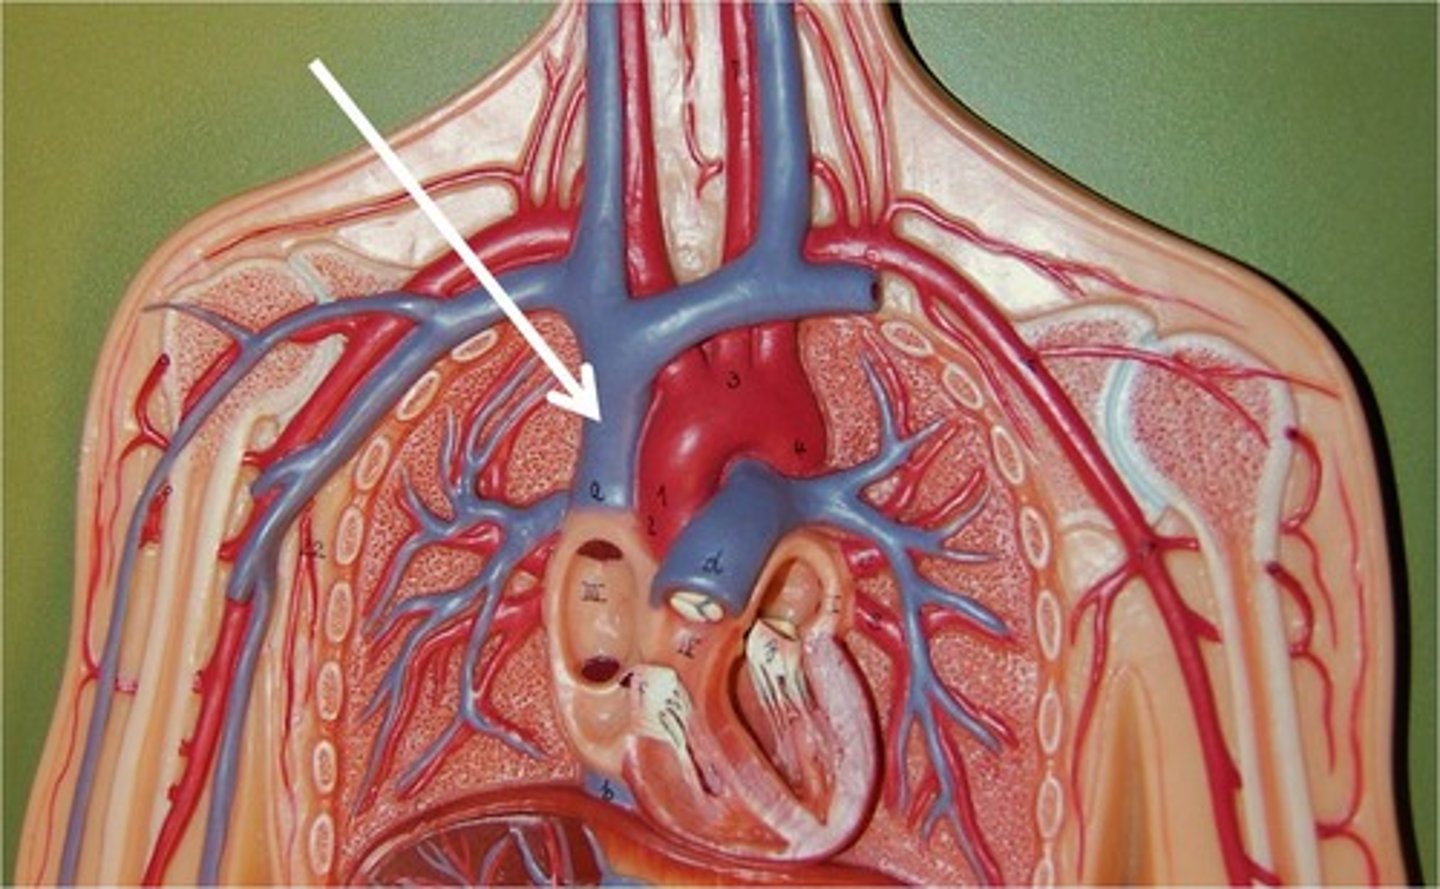

superior vena cava

inferior vena cava